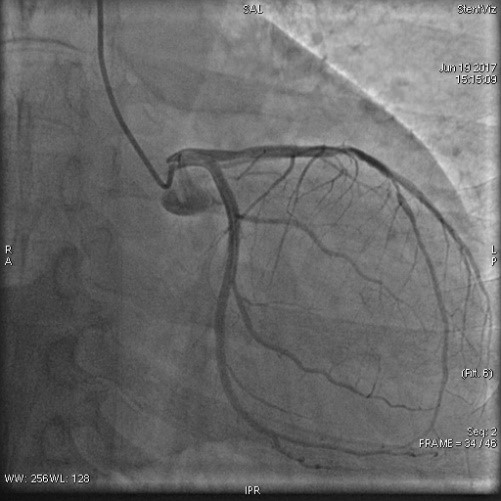

病例名称:支架精显功能在冠脉介入中的应用 病史: 男性,50岁 主因“间断胸痛半年,加重半天”入院。 曝光模式及参数: Dynamic,15f/s 造影表现: 经右桡动脉行CAG示:前降支中远段重度弥漫性狭窄。

治疗方案及结果: 前降支中远段重度弥漫性狭窄,行支架植入术治疗,术后罪犯血管开通,血流通畅,达TIMI3级。 病例点评及临床价值: 前降支近段支架释放后,发现支架球囊未完全扩张,后扩后情况未明显改善,应用StentViz示:前降支近段支架与远段支架重叠良好,近段支架近端未完全扩张,有“小腰”,呈“狗骨头效应”,同时血管局部钙化斑块明显。明确情况后,继续加压扩张后,支架完全扩张,血流通畅达TIMI3级。 在本病例中,术中StentViz即刻评价了支架释放效果,精准的显示了两支架扩张、重叠和贴壁的情况,把“几乎看不见的支架”精准的呈现了支架的每一个细节,同时也显示了透视和采集不易发现的钙化病变,提高了诊断的精准度,明确了进一步的治疗方案。